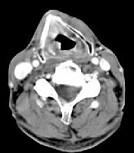

问题 男,63岁,咽喉部不适约1年,近2个月经常咳嗽,痰中带有血丝,CT如图所示,应诊断为()

选项 A.梨状窝癌 B.声门型喉癌 C.声门下型喉癌 D.声门上型喉癌 E.混合型喉癌

答案 D